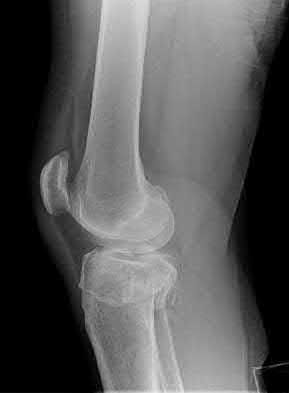

1. # A 32-year-old male sustains the injury shown in Figure A and undergoes treatment as shown in Figure B. Following placement of this implant, what is the best technique to confirm it is not too proud proximally?

1. Lateral radiograph of the knee

5. Internally rotated 45 degree view of the knee Corrent answer: 1

The safe zone for tibial nail placement as seen on radiographs is just medial to the lateral tibial spine on the anteroposterior radiograph and immediately adjacent and anterior to the articular surface as visualized on the lateral radiograph.

Tornetta et al specifically located the safe zone for nail entry in a study using fresh frozen cadaver knees. The authors found that the safe zone for nail placement is located 9.1+/-5 millimeters lateral to the midline of the plateau and three millimeters lateral to the center of the tibial tubercle. The width of the safe zone averaged 22.9 millimeters and was as narrow as 12.6 millimeters.

The starting point of the of the nail can be best viewed on the lateral knee radiograph, an example of which is shown in Illustration A. Illustration B shows the "sweet spot" for nail insertion as defined by Tornetta.